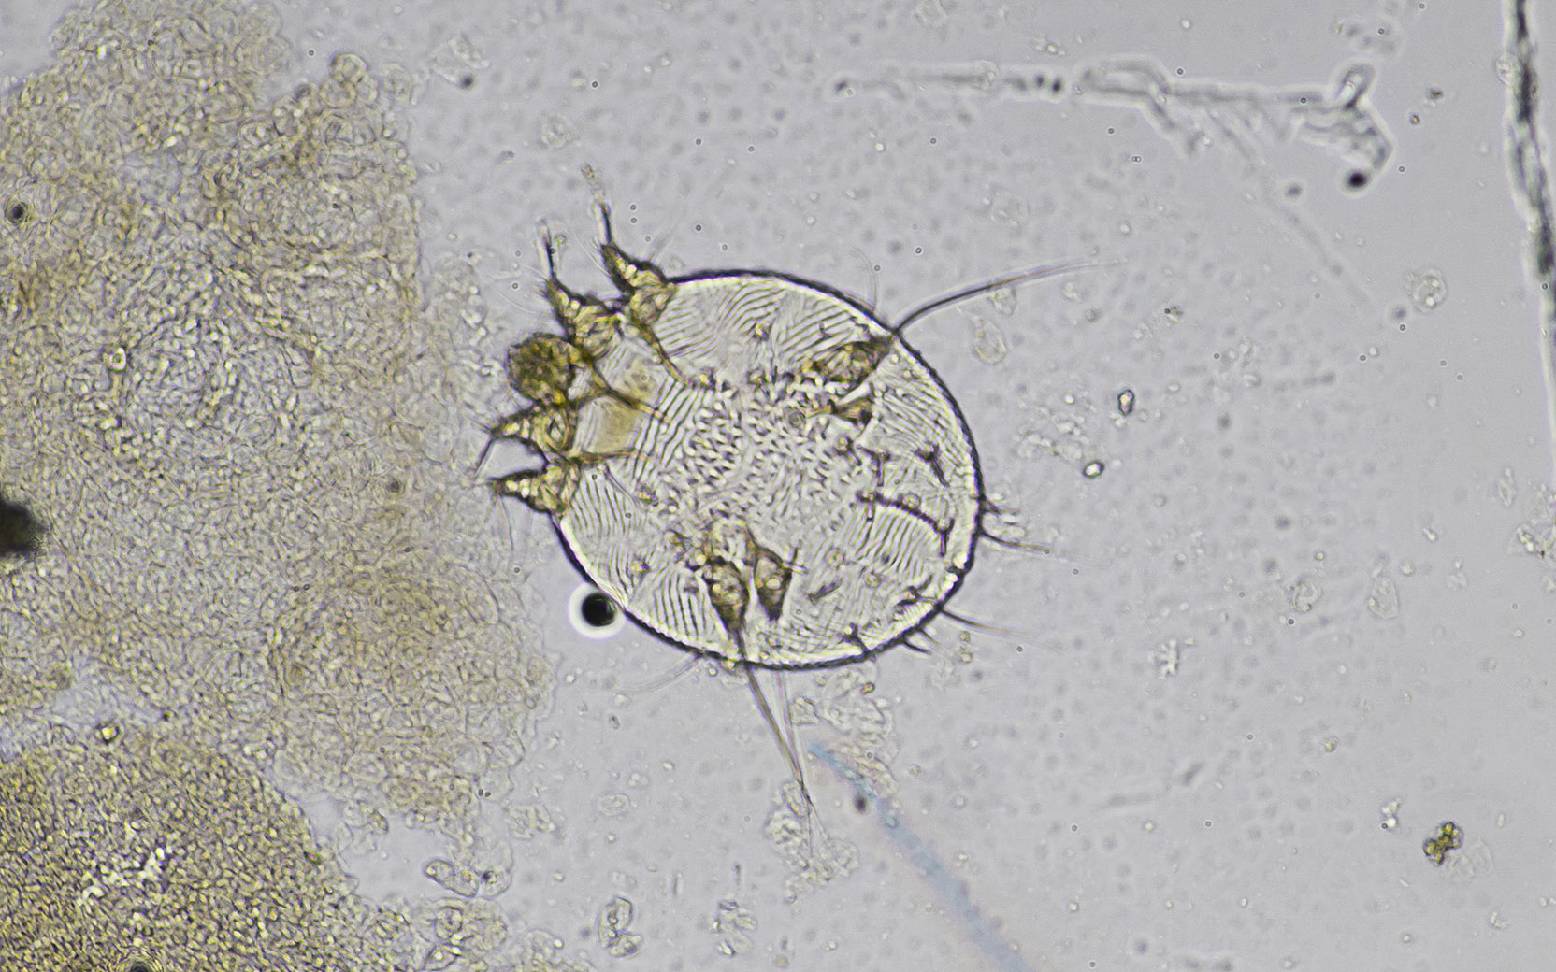

To confirm the clinical diagnosis, the veterinarian will take several large superficial skin scrapings and examine them under a microscope for mites. In addition, two to four weeks after infection, Sarcoptes-specific antibodies can be detected via a blood test.

Sarcoptes mites belong to the arachnid family and are only 0.2 to 0.4 mm in size. The males live on the surface of the skin, while the females burrow into the upper layers of the skin, which is why this mite species is also known as the burrowing mite. The females lay their eggs in the burrows, from which adult mites emerge within two to three weeks. The entire life cycle of the mite therefore takes place on the host.